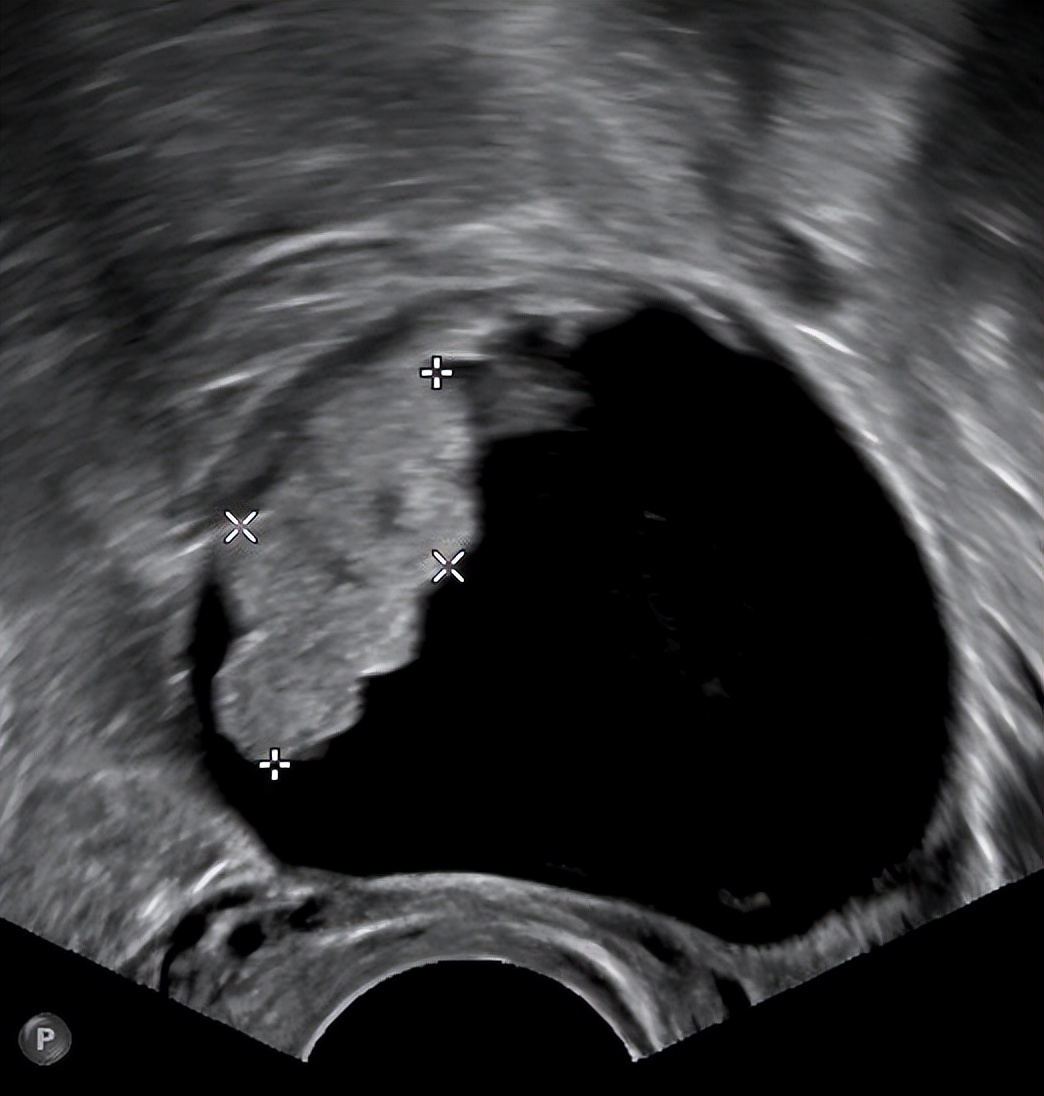

05、 卵巢子宫内膜异位囊肿

俗称“巧克力囊肿”,它跟巧克力没啥关系,是因为囊内咖啡色液体粘稠似巧克力而得名。当子宫内膜细胞异位生长到卵巢,随月经周期性出血就会形成“巧克力囊肿”。

卵巢子宫内膜异位囊肿的发生可能与经血逆流、淋巴及静脉扩散等因素相关。它主要会引发痛经、月经失调等症状,血清CA125水平常轻度升高。随着病情进展,还可能出现不孕、囊肿破裂等并发症,且有恶变的可能。虽然可以通过药物减缓其生长速度,但是最终仍需进行手术治疗。